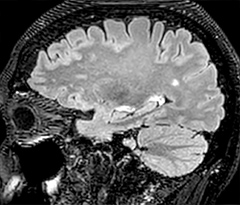

Improving scan time and/or spatial resolution

A two year follow-up scan of a CPA meningioma using both Ingenia 3.0T without CS and Ingenia Elition 3.0T with Compressed SENSE allows for a nice comparison to demonstrate the protocol improvements achieved on the Elition: 3D FLAIR has a shortened scan time, improved SNR and still the same spatial resolution. BrainView (3D T1 TSE) has improved spatial resolution and SNR with shortened scan time. For 3D T2 Drive the spatial resolution has been improved. 3D THRIVE used to have an interpolated 0.8 mm slice thickness, but true thickness at 1.6 mm, so that axial slices displayed a decent quality, but reformats were suboptimal.

Compressed SENSE is used on Elition to improve spatial resolution and reduce the non-interpolated slice thickness to allow smoothly reformatted images. Total scan time (adding SmartBrain and an additional b2000 diffusion) was 13:19 on Ingenia, and is now reduced to 10:42 on Ingenia Elition.

Ingenia 3.0T (without Compressed SENSE)

3D FLAIR (without Compressed SENSE)

3D FLAIR

1.0 x 1.0 x 1.0 mm*

4:24 min.

3D TSE T1w (without Compressed SENSE)

3D TSE T1w

1.0 x 1.0 x 1.2 mm*

2:40 min.

3D T2w Drive (without Compressed SENSE)

3D T2w Drive

0.8 x 0.8 x 1.0 mm*

3:05 min.

3D T1w THRIVE (without Compressed SENSE)

3D T1w THRIVE

0.8 x 0.8 x 1.6 mm*

1:30 min.

Ingenia Elition 3.0T with Compressed SENSE

3D FLAIR (with Compressed SENSE)

2:50 min.

3D TSE T1w (with Compressed SENSE)

2:10 min.

3D T2w Drive (with Compressed SENSE)

0.7 x 0.7 x 0.7 mm*

2:52 min.

3D T1w THRIVE (with Compressed SENSE)

0.7 x 0.7 x 0.8 mm*

*true voxel size, without interpolation